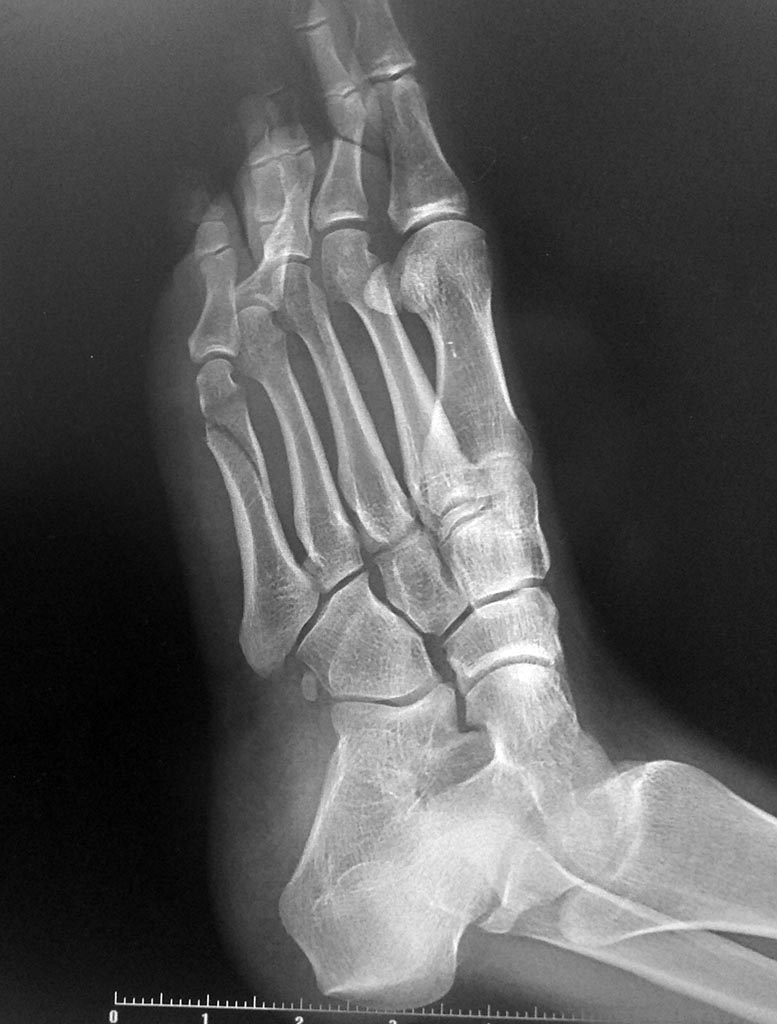

Косой перелом пятой плюсневой кости

40 дней после перелома

Получил травму ступни при легкой разминке перед бегом - оступился на внешнюю сторону стопы.

Приложил холод и поехал в районный травмпункт. Сделал рентген.

Врач поставил диагноз: "З/перелом 5 плюсневой кости б/с". Снимок мне, увы, не показал. Наложил лангету.Лечение - иммобилизация, без нагрузки, кальций+д3.

Сегодня 40 день (почти 6 недель) с момента перелома, сделали повторный снимок. И неожиданно врач говорит что "смещение стало меньше" и "сращение недостаточно". И прописал еще две недели в лангете. Однако при этом советует отказаться от костылей и ходить опираясь ПОЛНЫМ весом на всю ступню (а не только пятку, например). При этом у меня до сих пор сильные боли в районе мизинца (сбоку и снизу стопы) и гематома в половину ступни в районе трех центральных пальцев.

Прикладываю снимки рентгена на 40 день перелома.

Перелом срастается в приемлемом положении.

Можно увеличивать нагрузку на ногу в пределах переносимого. Смысла в гипсовой шине при полной нагрузке не видно - гипс немедленно сломается.

По мере того, как уйдут болезненные проявления, можно будет возвращаться к спортивным нагрузкам.